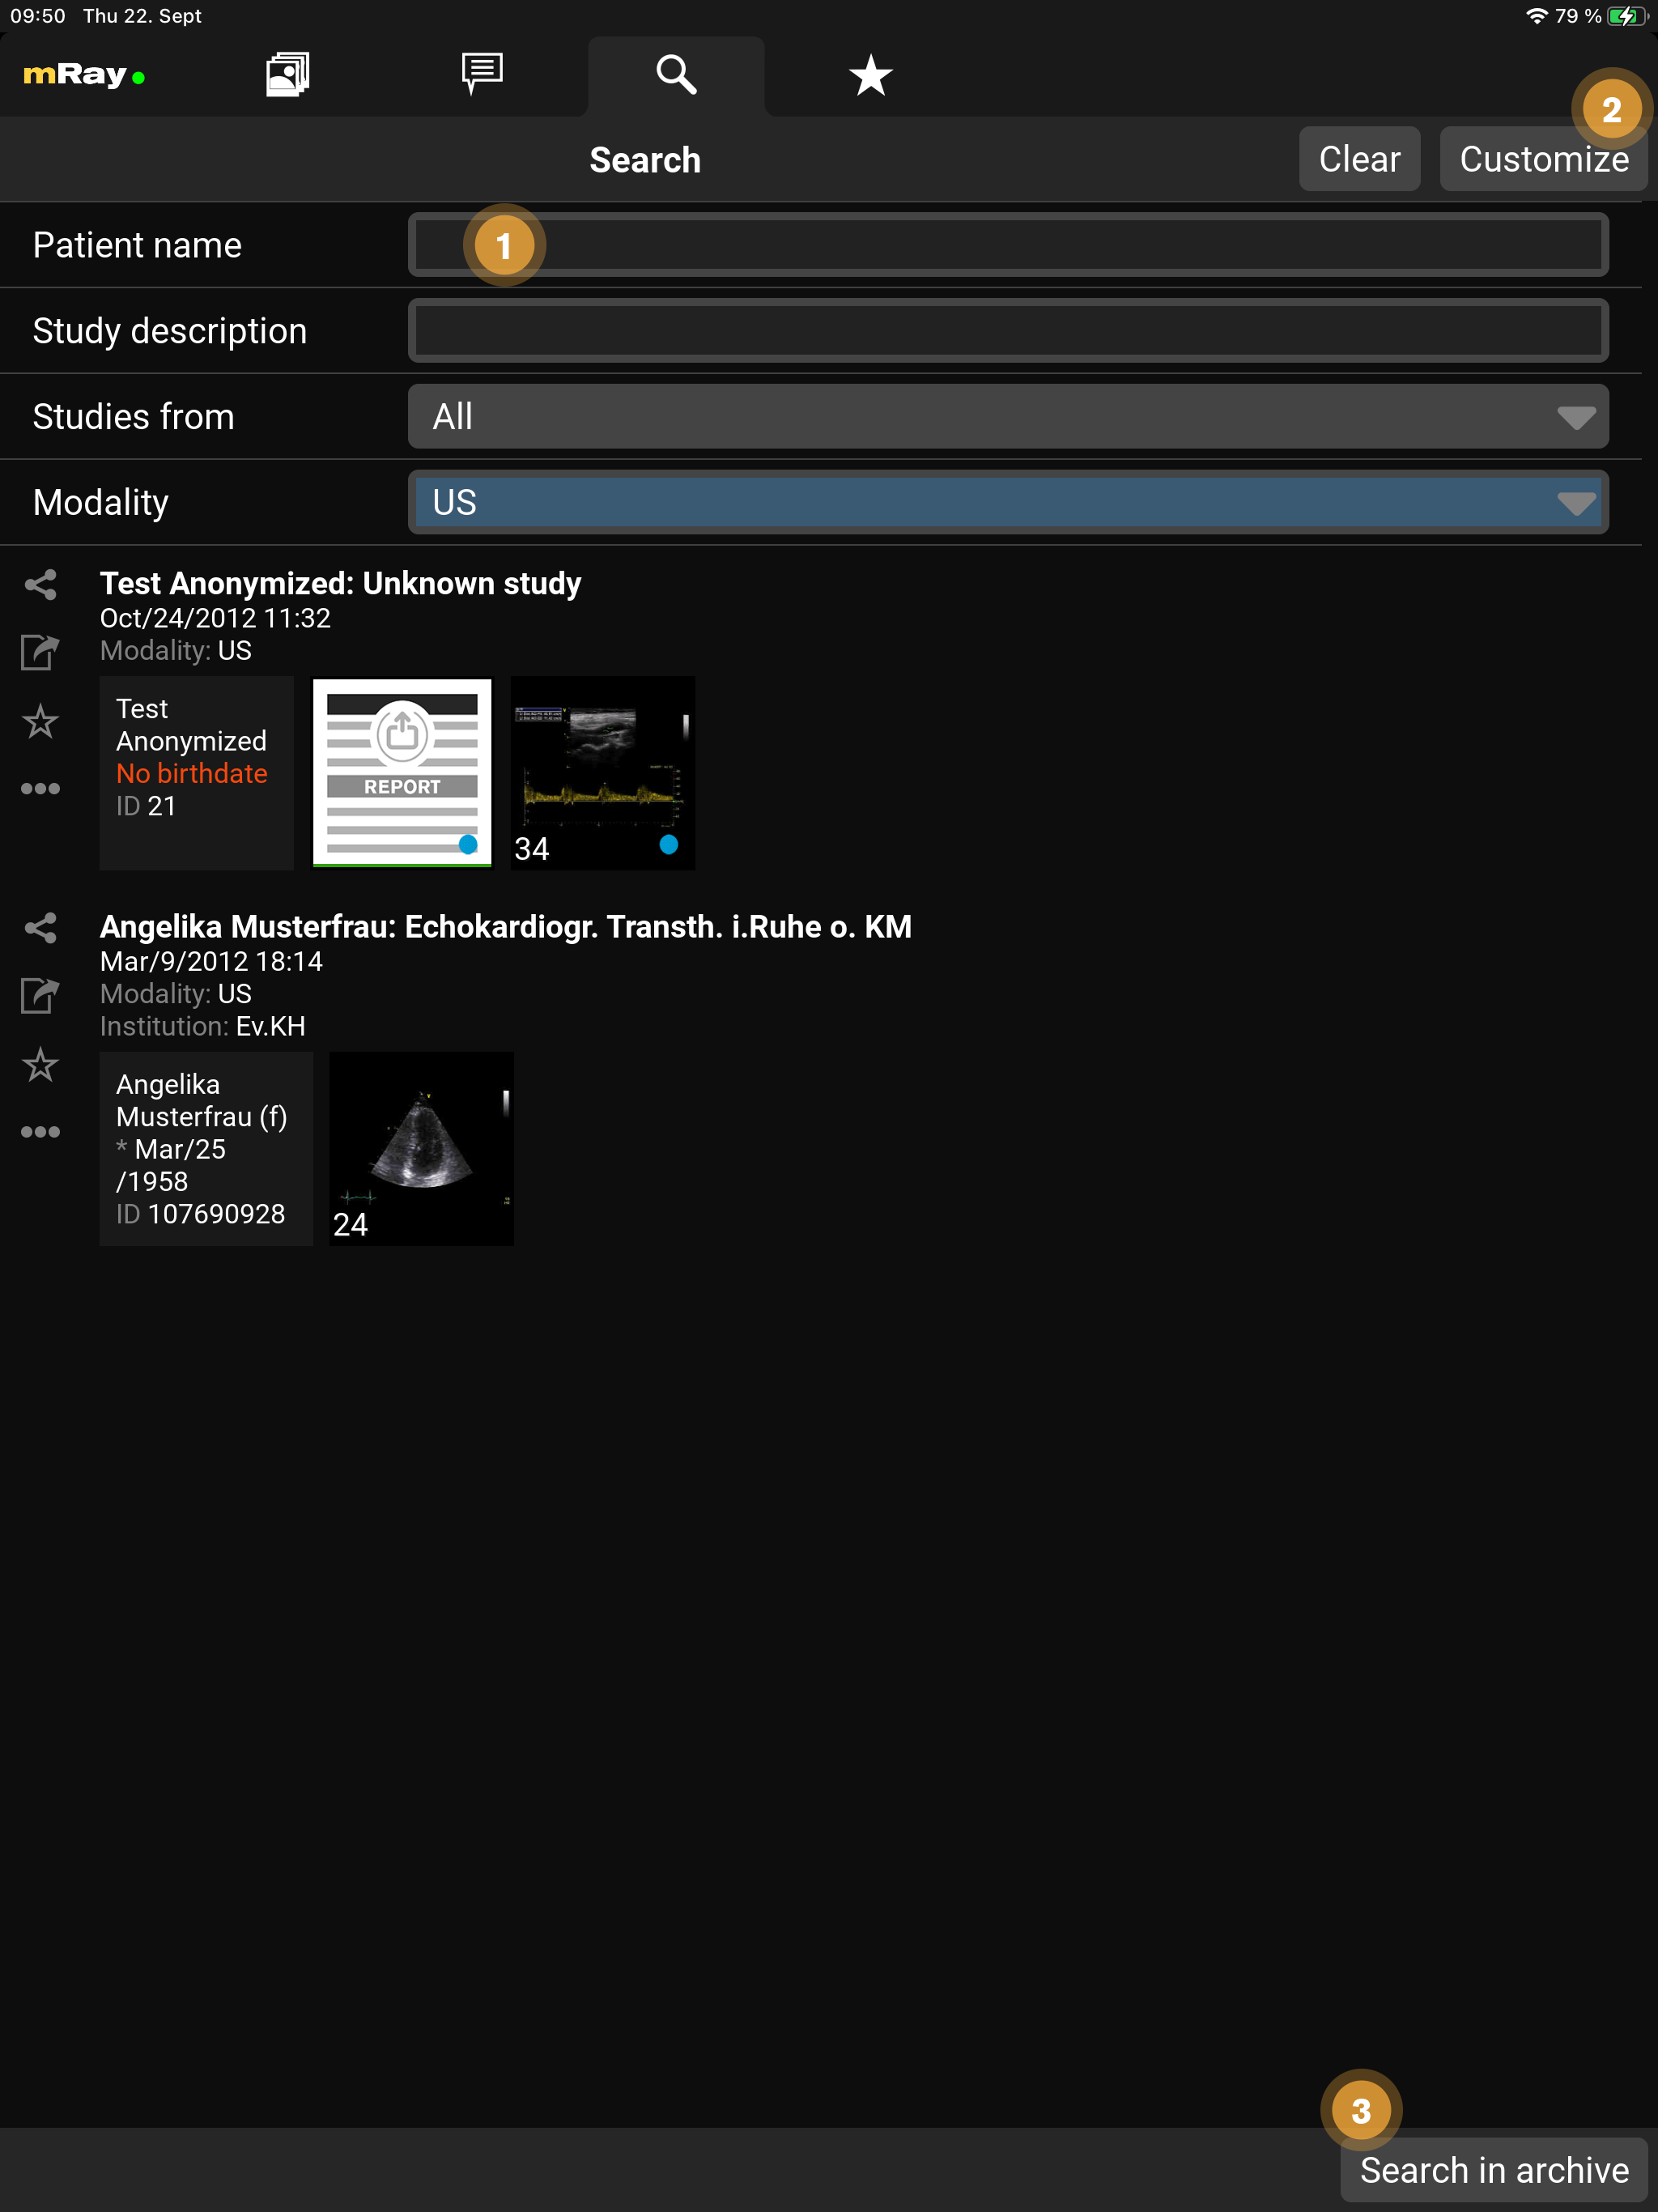

9.11. Suche

Mit der Suche Funktion können Sie im Datenbestand ihres mRay Servers schnell und einfach suchen. Die Ergebnisliste zeigt Studien auf die ihre Suchkriterien zutreffen. Die Suchergebnisse können über den "Offline verfügbar" Button in die Inbox verschoben werden. Sie können in der Suche Datensätze auch direkt anschauen oder einfach mit einem Kollegen Teilen. Beachten Sie, dass natürlich nur solche Datensätze erscheinen, auf die Sie auch Zugriffsberechtigungen erhalten haben. Sollte der gewünschte Datensatz nicht in der Liste auftauchen, besteht die Möglichkeit über ein oder mehrere angeschlossene PACS eine entsprechende Anfrage zu stellen. Die Suchfelder lassen sich außerdem nach Ihren Bedürfnissen anpassen.

-

Spezifizieren Sie hier Ihre Suchanfrage

-

Die Suchfelder lassen sich über diesen Button anpassen

-

Senden Sie die Suchanfrage an ein PACS (verfügbar falls Ihr mRay Server entsprechend konfiguriert ist

Die Suchfelder lassen sich anpassen und folgende Felder stehen zur Auswahl:

|

Hinweise zur PACS-Suche

|

|

Bitte beachten Sie folgenden generellen Hinweis zur PACS-Suche

mRay leitet die von Ihnen gemachten Eingaben an ihr PACS weiter. Wenn Sie also sog. Wildcards (*/?) verwenden wollen, können Sie das genauso wie aus Ihrer gewohnten PACS-Umgebung. Lediglich für das Name-Feld werden standardmäßig das Wildcard-Zeichen „*“ angehängt. Wenn Sie keine Angabe machen, wird das Feld bei der Anfrage ignoriert. |